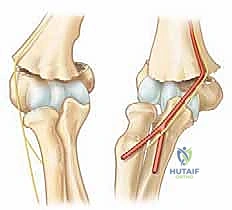

لفهم طبيعة هذه الإصابة، يجب أولاً تفكيك المصطلح الطبي. "عظم العضد" (Humerus) هو العظم الطويل الممتد من الكتف وحتى الكوع. في نهايته السفلية (البعيدة)، يتسع العظم ليشكل ما يُعرف بـ "اللقمتين" (Condyles) اللتين تتفصلان مع عظام الساعد (الكعبرة والزند). المنطقة التي تقع "فوق اللقمة" (Supracondylar) هي منطقة انتقال ضيقة ورقيقة جداً في العظم، وتشبه في شكلها عنق الساعة الرملية.

تمر ثلاثة أعصاب رئيسية عبر مفصل الكوع لتغذية الساعد واليد. هذه الأعصاب عرضة للإصابة بشكل كبير في كسور فوق اللقمة:

* العصب المتوسط (Median Nerve) وفرعه الأمامي بين العظام (AIN): يمر أمام الكوع. العصب الـ AIN هو الأكثر عرضة للإصابة في كسور النوع الانبساطي المتزحزحة للخلف. إصابته تؤدي إلى عدم قدرة الطفل على ثني المفصل الأخير من إصبعي الإبهام والسبابة (علامة OK sign).

* العصب الكعبري (Radial Nerve): يمر على الجانب الخارجي للكوع. إصابته تؤدي إلى "تدلي المعصم" (Wrist Drop) وعدم القدرة على رفع اليد للأعلى.

* العصب الزندي (Ulnar Nerve): يمر خلف الكوع في نفق عظمي. يكون عرضة للإصابة في كسور النوع الانثنائي، أو كإصابة علاجية المنشأ (Iatrogenic) أثناء إدخال الأسلاك المعدنية من الجهة الداخلية للكوع.

3. الأوعية الدموية (الشريان العضدي)

الشريان العضدي (Brachial Artery) هو الوعاء الدموي الرئيسي الذي يغذي الذراع بأكملها، ويمر مباشرة أمام عظم العضد في منطقة الكوع. في الكسور المتزحزحة بشدة (النوع الثالث)، يمكن لحافة العظم المكسور الحادة أن تضغط على الشريان، أو تسبب تشنجاً وعائياً، أو حتى تمزقه. هذه حالة طوارئ طبية قصوى تُعرف بـ "نقص التروية" (Ischemia)، وإذا لم تُعالج فوراً قد تؤدي إلى متلازمة الحيز (Compartment Syndrome) وتقلص فولكمان الإقفاري (Volkmann's Ischemic Contracture)، مما يؤدي إلى فقدان دائم لوظيفة اليد.